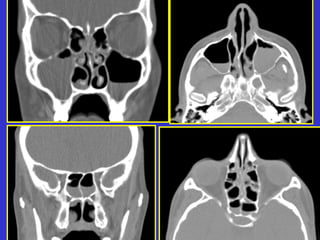

Este documento describe las diferentes proyecciones radiográficas utilizadas para examinar los senos paranasales, incluyendo las proyecciones básicas de Caldwell, Waters lateral y las proyecciones especiales como Hirtz y Waters mentonasal. También describe las diferentes estructuras anatómicas que componen el complejo ostiomeatal anterior y posterior de los senos paranasales.